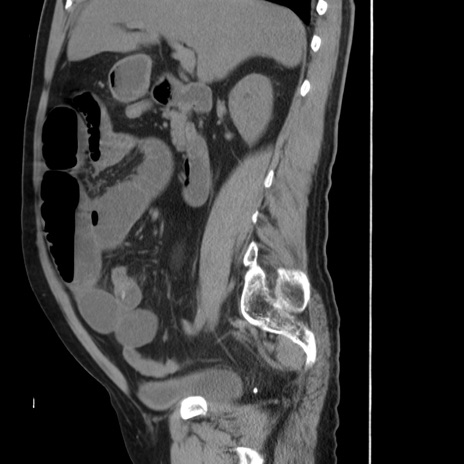

冠状断像

【症例】 60歳代男性

【主訴】 腹部膨満、嘔吐

【現病歴】5日前頃より倦怠感を認め食事量減少し4日前の朝嘔吐、食事摂取困難となった。 3日前近医受診し点滴施行され整腸剤などを処方された。 当日他院を受診し、腹部膨満著明、炎症反応の上昇(CRP10.8、WBC11200)あり、紹介受診となる。

【身体所見】 意識JCS1 受け答えがはっきりしないBP 111/57mHg、 P 67bpm、、BT35.2°C、SpO2 97%(RA)、 腹部:膨隆、打診で鼓音あり、全体的に圧痛有り、腸蠕動音(-)、反跳痛ははっきりせず。

【データ】WBC 11400、CRP 14.20